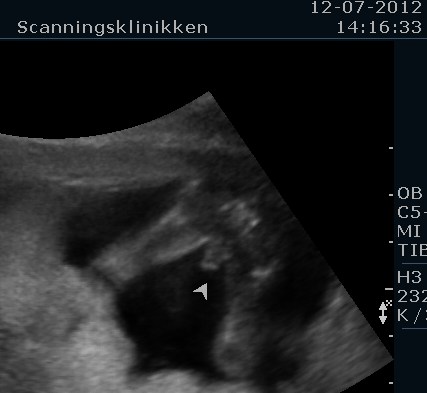

Her er et par billeder. Det første billede viser at man slet ikke er i tvivl om at det er en dreng og det andet billede viser at han har det sødeste lille fine hoved med runde kinder og kyssemund